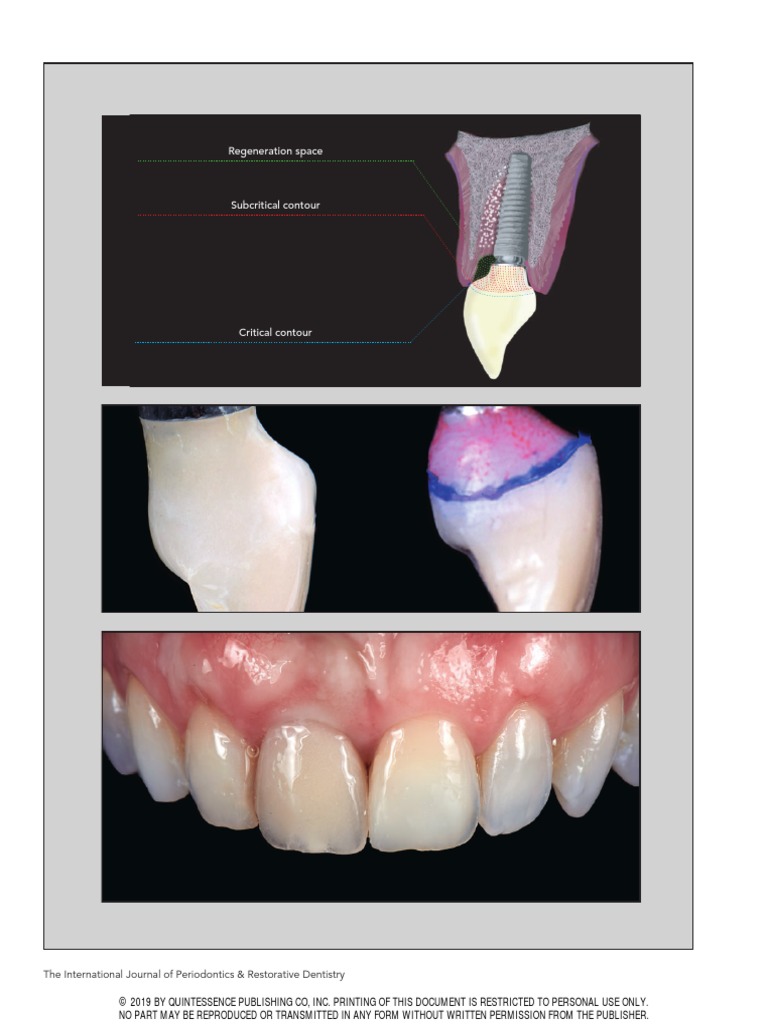

Regeneration space

Subcritical contour

Critical contour

Fig 1  Maintenance of a regenerative space while avoiding soft and hard tissue

conjunction with undesirable compression is mandatory when placing a provisional restoration on an immediate implant.

crestal gingival complex should Fig 2  Clinical guidelines for contour management of immediate provisional restorations.

bone and/or soft tissues (Fig 1). whereas facially it could be dimensions is key to obtaining